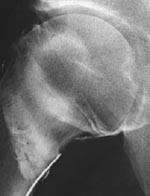

Etter at det er tatt konvensjonelle røntgenbilder av det aktuelle hofteleddet, blir pasienten lagt på ryggen på et gjennomlysningsbord. En assistent står ved fotenden og trekker i ekstremiteten samtidig som den blir rotert innover. Dette frembyr en liten utposning av leddkapselen medialt ved collum femoris som vil være lett tilgjengelig for punksjon. Under sterile forhold rettes en 20 gg nål ved hjelp av gjennomlysning mot dette området. Man stikker lateralt for a. femoralis. Det settes forsiktig 1 % Xylocain. Hvis man ikke kjenner noen motstand under instillasjonen, er nålen sannsynlig plassert intraartikulært. For å verifisere dette settes det forsiktig ikke-ionisk kontrastmiddel (fig 1). Dersom kontrastmidlet legger seg rundt collum og caput femoris, settes det fortynnet gadolinium (fortynnet til 0,2 mmol/l). I alt settes det 6 – 8 ml væske. Pasienten får beskjed om å bevege hoften. Et røntgenbilde tas for å verifisere at nålen er kommet intraartikulært og for å se etter eventuelle større patologiske forandringer, som avansert synovitt eller større frie legemer.

Acetabulær labrum-skade er en av flere årsaker til kroniske hofteleddssmerter hos pasienter med tidligere hoftetraume eller hofteleddsdysplasi, men sees også hos pasienter uten tidligere kjent skade eller dysplasi. Hoftesmertene er ofte ledsaget av et klikk eller en kneppende lyd ved bevegelse. Av og til har pasientene en følelse av at hoften ”gir etter”. Konvensjonelt røntgenbilde av hofteleddene er som oftest helt negative eller kan vise dyplastiske forandringer uten at man får noen informasjon om labrum. I vårt materiale var det en pasient med lette dyplastiske forandringer, men hvor labrum var helt normal ved MR-artrografi.